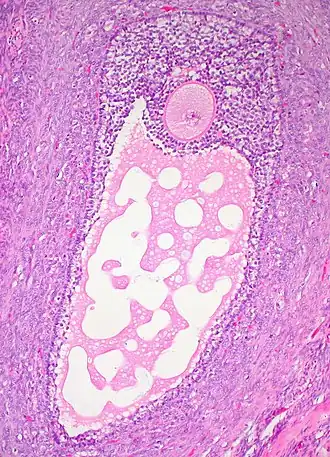

![]() Histology section of a mature ovarian follicle. The oocyte is the large, round, pink-staining cell at top center of the image. | |

Ovarian follicles are the basic units of female reproductive biology. Each of them contains a single oocyte (immature ovum or egg cell). These structures are periodically initiated to grow and develop, culminating in ovulation of usually a single competent oocyte in humans.[5] They also consist of granulosa cells and theca of follicle.

The granulosa cells, in turn, are enclosed in a thin layer of extracellular matrix – the follicular basement membrane or basal lamina (fibro-vascular coat in picture). Outside the basal lamina, the layers theca interna and theca externa are found.